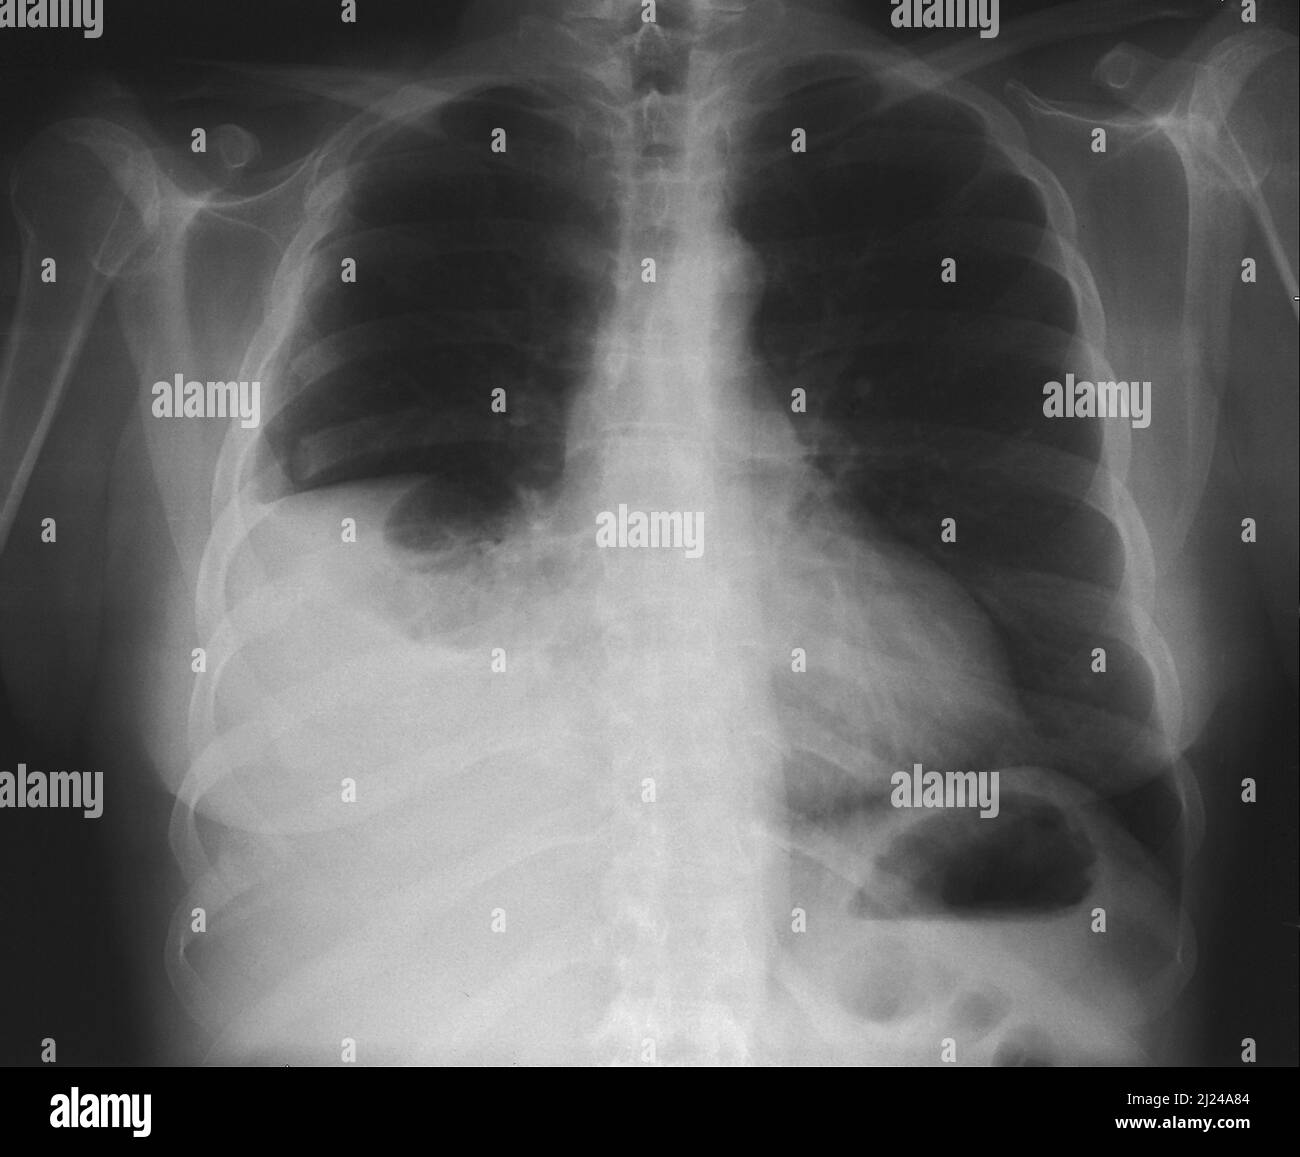

Fractured ribs and pleural effusion, Xray Stock Photo Alamy Rib Fracture With Pleural Effusion  Alicia j mangram 1 * , nicolas zhou 2 , 3 , jacqueline. Traumatic rib fractures are the consequence of significant forces impacting the chest wall and are most commonly due to blunt. In this article, we review risk factors for morbidity and complications, intervention strategies, and discuss experience with bundled clinical pathways for rib fractures. Rib injuries can be. Rib Fracture With Pleural Effusion.

Fractured ribs and pleural effusion, Xray Stock Image C055/1115 Rib Fracture With Pleural Effusion  Traumatic rib fractures are the consequence of significant forces impacting the chest wall and are most commonly due to blunt. Are we being aggressive enough? We present what we believe to be the first case of rib fixation as a successful. We sought to investigate the characteristics of rib fracture dpf, its associated outcomes, and implications for management in these. Rib Fracture With Pleural Effusion.